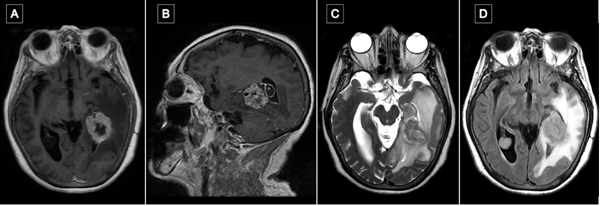

Transcurrido un mes de la cirugía, se realizó resonancia magnética de encéfalo con gadolinio en la que se observó en la región temporomesial izquierda un área de señal líquida con signos de gliosis periférica y sutiles restos de hemosiderina, sin evidencia de lesión tumoral residual. Persistía el edema vasogénico con efecto de masa sobre el sistema ventricular ipsilateral (Figura 6).

Figura 6. Comparación de resonancias magnéticas pre y postquirúrgicas. A y B) RM prequirúrgica de encéfalo, cortes axial y sagital, respectivamente, en secuencia T1 contrastada, se evidencia lesión expansiva con realce heterogéneo localizada en topografía temporomesial izquierda. C y D) RM de encéfalo con gadolinio realizada aproximadamente un mes luego de la intervención quirúrgica. Cortes axial y sagital, respectivamente, en secuencia T1 contrastada en la que se evidencia en región temporomesial izquierda un área de señal líquida con signos de gliosis periférica, sin evidencia de lesión tumoral residual.